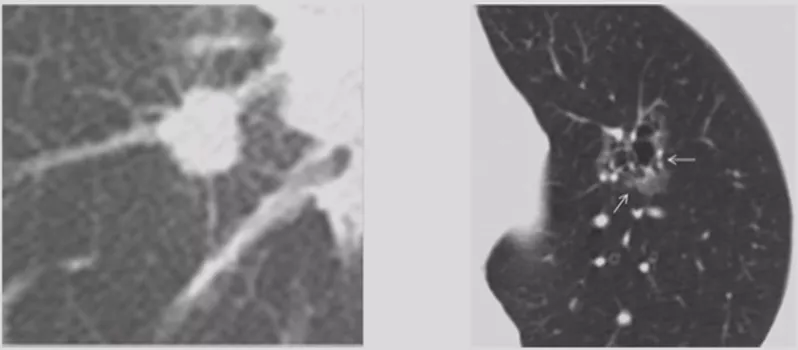

在临床上经常手术切除后发现是AAH,关于AAH的病人是否需要手术还存在很大的争议,有的认为不需要手术,观察就可以。那么我们在术前怎么评判是否为AAH?其实具有一定特征。一般来说,多位于肺外周,多<5mm,圆形或类圆形,边界清楚,多发更常见,绝大部分是均匀的纯磨玻璃影,里边没有实性成分。组织学检查AAH呈轻度到中度非典型立方柱状上皮细胞沿肺泡和呼吸性细支气管上皮增殖,无浸润,这样在临床上诊断AAH应该没有问题。但是,如下图所示,这个病人是多灶性病变,现在多灶性结节有所增多,会给临床的处理上带来一定压力。

原位癌(AIS)

接下来再发展就是原位癌。一般来说,多位于肺外周,多为单发,病灶比AAH更大,形状可为圆形、类圆形或不规则,边界清楚,可为纯磨玻璃影。现在计算机可以测量CT值,我们应该定量分析,观察CT值,不透明程度较AAH高。组织学呈纯粹的贴壁生长,无基质、血管或胸膜浸润。一旦遇到密度稍微高一点的磨玻璃结节,要谨慎,它很可能已经是原位癌,此时手术仍然是非常理想的效果。